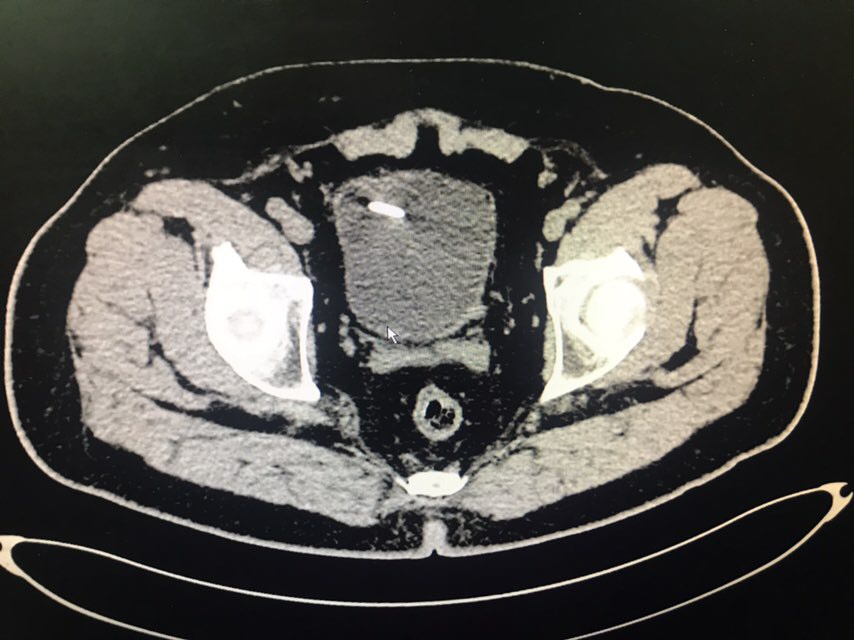

查体:无特殊。辅助检查:全腹CT(我院2018-8-6):右肾盂、肾盏及右输尿管上段明显扩张、积水;右侧输尿管置管。左肾盏区点状结石;双肾囊肿可能。膀胱充盈,壁稍增厚、毛糙,合并炎症可能,胆囊结石。脂肪肝;肝右叶小钙化灶。

从患者CT片子上看,患者右侧输尿管下段狭窄,输尿管支架管返折,因膀胱镜下未能成功取出,故行右侧输尿管探查术。手术顺利,术后给予曲克芦丁脑蛋白水解物注射液5ml治疗,患者术后恢复良好。